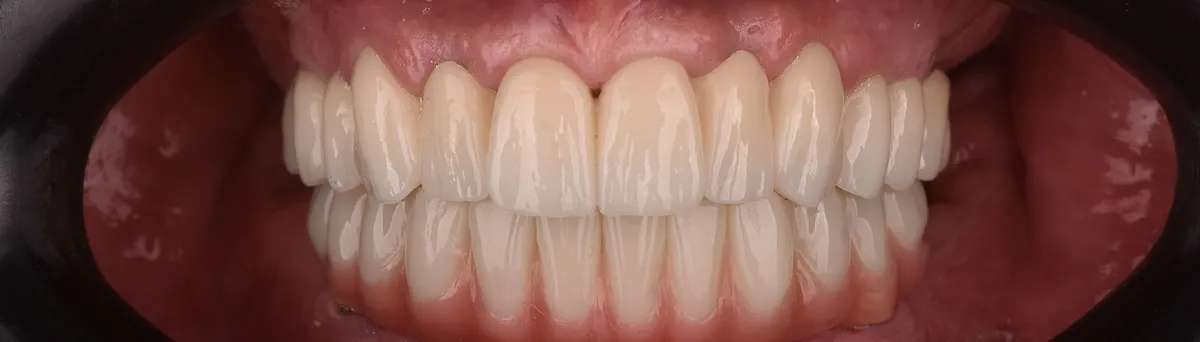

Pacijentica je došla u IMED zbog lošeg stanja u čeljusti, a nakon prvog pregleda preporučen joj je FP1 All-on-4 zahvat u gornjoj i donjoj čeljusti.

Zahvat je izveden u općoj anesteziji za maksimalnu udobnost i sigurnost pacijentice tijekom cijelog postupka, a nakon ugradnje implantata postavljen je trajni cirkonski rad bez umjetnog zubnog mesa u gornju čeljust, te metal-kompozitni rad u donju čeljust.

FP1 rješenje namijenjeno je pacijentima s dovoljno vlastite kosti u čeljusti te omogućuje iznimno prirodan izgled i vrhunsku funkcionalnost.